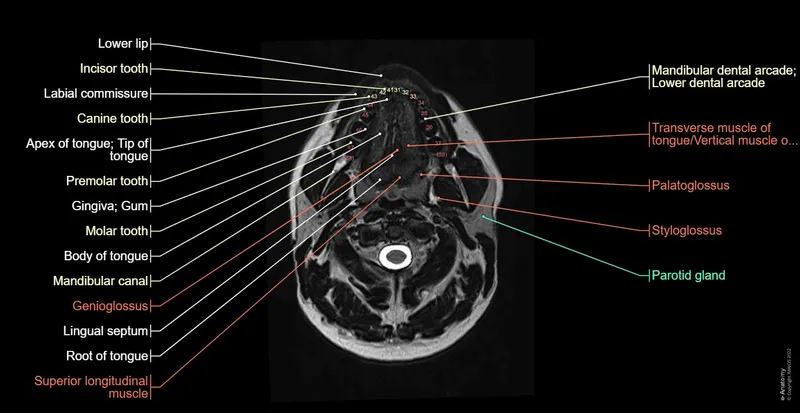

Axial Views - A Slice-by-Slice Tour

- Superior to Inferior Progression: A systematic approach to reading head & neck scans, moving from the skull base down to the thoracic inlet.

- Each slice reveals specific anatomical relationships critical for localizing pathology.